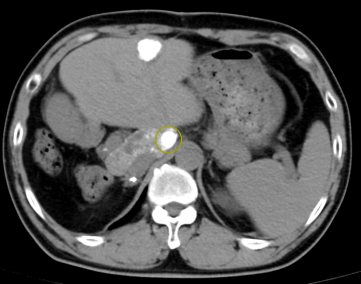

接受动脉化疗栓塞术后复查CT提示肿瘤病灶内碘化油沉积良好,为进一步行无水酒精消融治疗创造了条件,可在CT引导下行经皮穿刺无水酒精消融治疗

图片

介入栓塞后肿瘤病灶内碘化油沉积